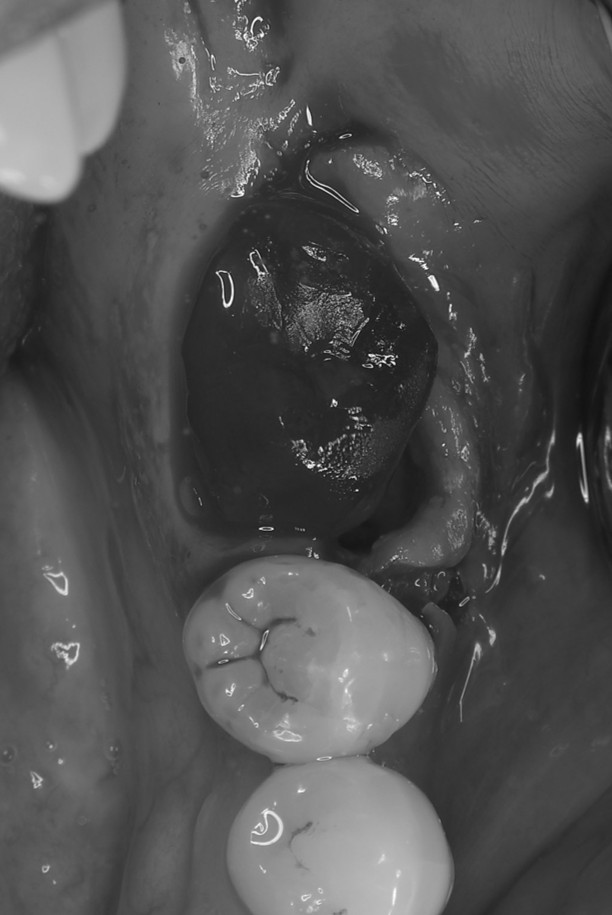

症例4

右下親知らずを右下第二大臼歯へ移植

| 患者様データ | 20代 女性 |

| 来院時の主訴 | 「右下奥歯で噛むと痛い。」 |

| 医院の診断 | 歯根破折 |